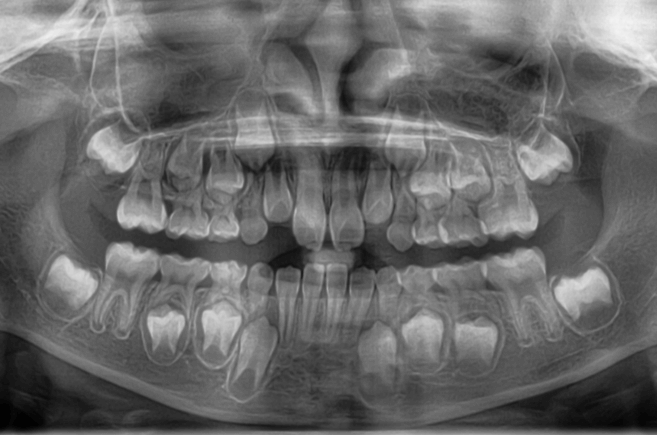

| 年齢・性別 | 8歳3ヶ月の男児 |

|---|---|

| 主訴 | 上顎前歯の位置異常に不安を抱え、歯並びと将来的な咬合状態を整える目的で来院された患者様です。 特に左側の前歯(中切歯および側切歯)の萌出が確認できないことがきっかけとなりました。 |

| 治療期間・回数 | 約5年10ヶ月 |

| 費用 | 460,000円(税別) |